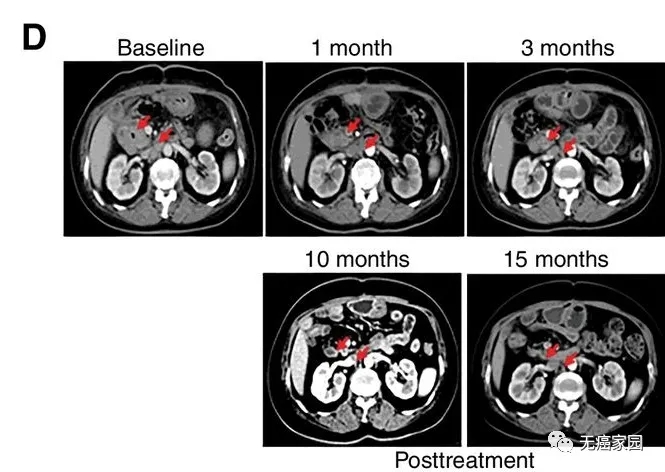

研究结果显示,17例患者可评估,其中1例胆管癌患者的肿瘤完全消失,截止到目前疗效已经保持了22个月,尚未发现疾病复发。10例患者疾病稳定,疗效保持2.5~15.5个月,中位无进展生存期为4个月。

CART-RGFR细胞治疗之前和1、3、10和15个月患者1的CT扫描图像。

红色箭头表示原发肿瘤和腹膜后淋巴结转移。